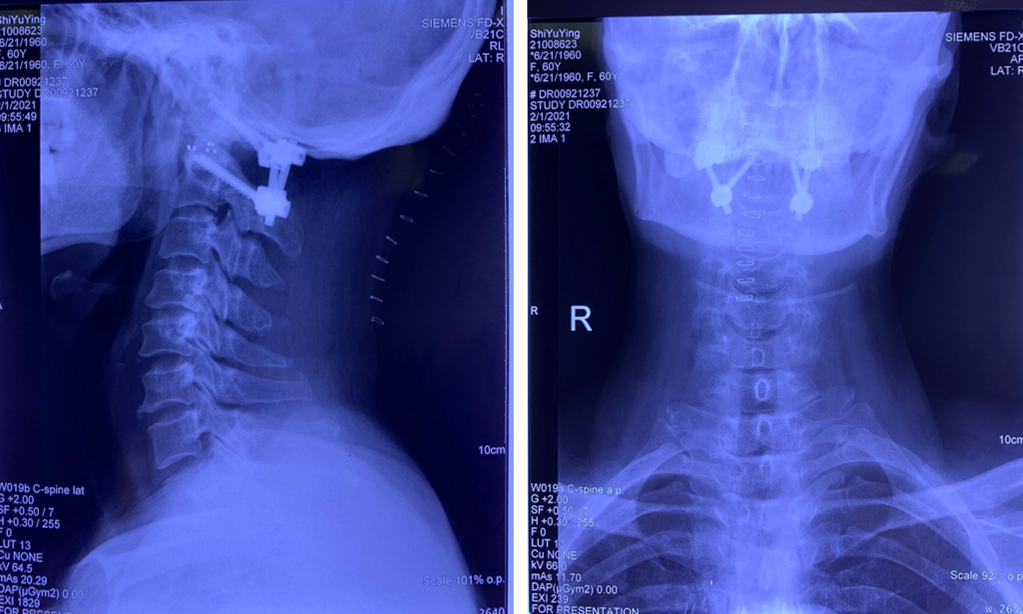

术后复查枕颈X线、CT、MR结果

影像学检查显示齿状突复位良好,脊髓减压充分